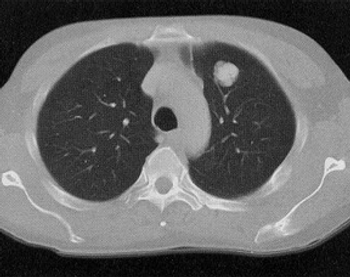

The NeXT Personal platform identified minuscule amounts of ctDNA that were found to be predictive of OS and RFS outcomes in patients with lung adenocarcinoma.